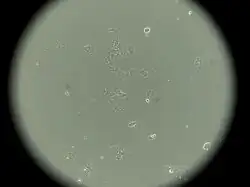

Characteristics of MCF-7 cells

MCF-7 cells have the following characteristics:[2][5][6][7][8][9]

- Primary tumor (invasive breast ductal carcinoma)

- Originate from pleural effusion

- Estrogen receptors present[10]

- Proliferative response to estrogens

- Presence of progesterone receptors

- Cannot have ERBB2 gene amplification (with Her2/neu protein overexpression)

- Tumorigenic in mice but only with estrogen supplementation if engrafted into the subcutaneous fat or mammary fat pad

- Tumorigenic in mice without estrogen supplementation if engrafted intraductally[11]

- Luminal epithelial phenotype

This cell line retained several characteristics of differentiated mammary epithelium, including the ability to process estradiol via cytoplasmic estrogen receptors and the capability of forming domes.